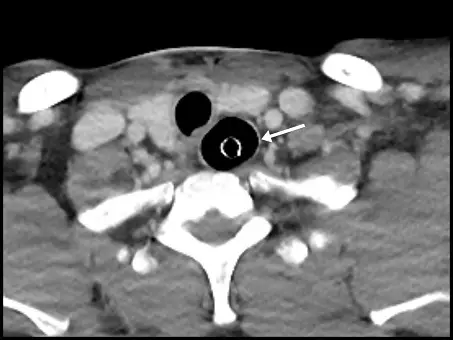

觀察此張下頸部/上胸部橫斷面無顯影劑電腦斷層影像(Axial non-contrast CT):

- 氣管(Trachea):位於影像中央偏前方,呈圓形且充滿空氣(低密度黑影)的結構。正常情況下,若插管成功,氣管內管應位於此處。但在本圖中,氣管內部並無任何管狀結構。

- 食道(Esophagus):位於氣管後方、脊椎體前方,解剖上通常略偏左側。在正常情況下,食道多呈現塌陷的軟組織構造。然而,本圖中該處明顯被空氣撐開。

- 管路結構(Endotracheal tube):白色箭號所指處為一高密度(亮白)的完整環狀結構,內部與周圍皆包覆著空氣。這個環狀影像即為氣管內管(Endotracheal tube, ETT)的橫切面。

- 綜合判斷:氣管內管並未放置於前方的氣管內,而是錯置於後方的食道中,導致食道異常擴張,此為典型的「食道插管(Esophageal intubation)」影像表現。

- (A) 食道插管(esophageal intubation):正確。由影像可清晰看見氣管內管(白色箭號指的環狀結構)位於氣管後方的食道腔內,而前方的氣管則是空無一物,為明確的食道插管證據。

在急救與困難呼吸道處置中,意外將氣管內管插入食道(Inadvertent esophageal intubation)是致命且必須立刻排除的併發症。從解剖學角度來看,氣管位於頸部前方,食道緊貼其後方。此 CT 影像精準捕捉到了氣管內管誤入食道的橫斷面:前方的氣管(Trachea)呈現空腔,無管路置入;後方的食道(Esophagus)則被管路與空氣異常撐開,箭號精準指在食道內的氣管內管管壁上。因此,最適當的敘述為食道插管。

- 食道插管影像徵象:若在 CT 上發現氣管空無一物,且食道內出現環狀管路並伴隨食道或胃部異常大量積氣,即確診為管路錯置(Malposition)。